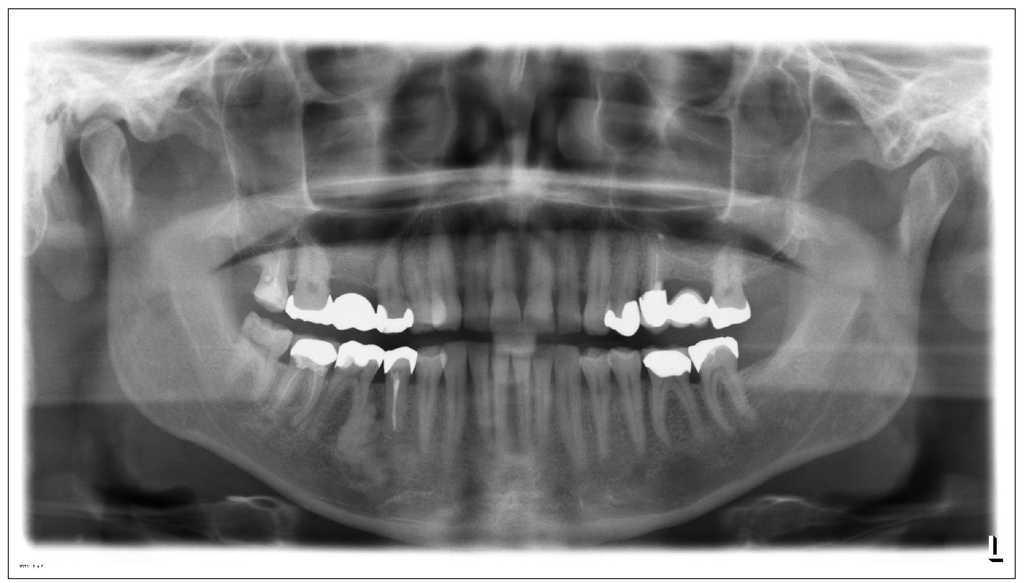

La radiografía panorámica obtenida en la visita del paciente mostró una alteración radioopaca, dismórfica y relativamente bien delimitada en la raíz mesial del diente 46 (fig. 1). La alteración se encuentra rodeada por un borde hipodenso delgado, sobre todo en las porciones superior y mesial. Se observan además osteólisis periapicales en las raíces mesial y distal del diente 47. Se practicó una tomografía volumétrica digital (TVD) dental preoperatoria para la planificación de la intervención quirúrgica y para localizar el conducto dentario inferior del lado derecho.

Figura 1. Radiografía panorámica.